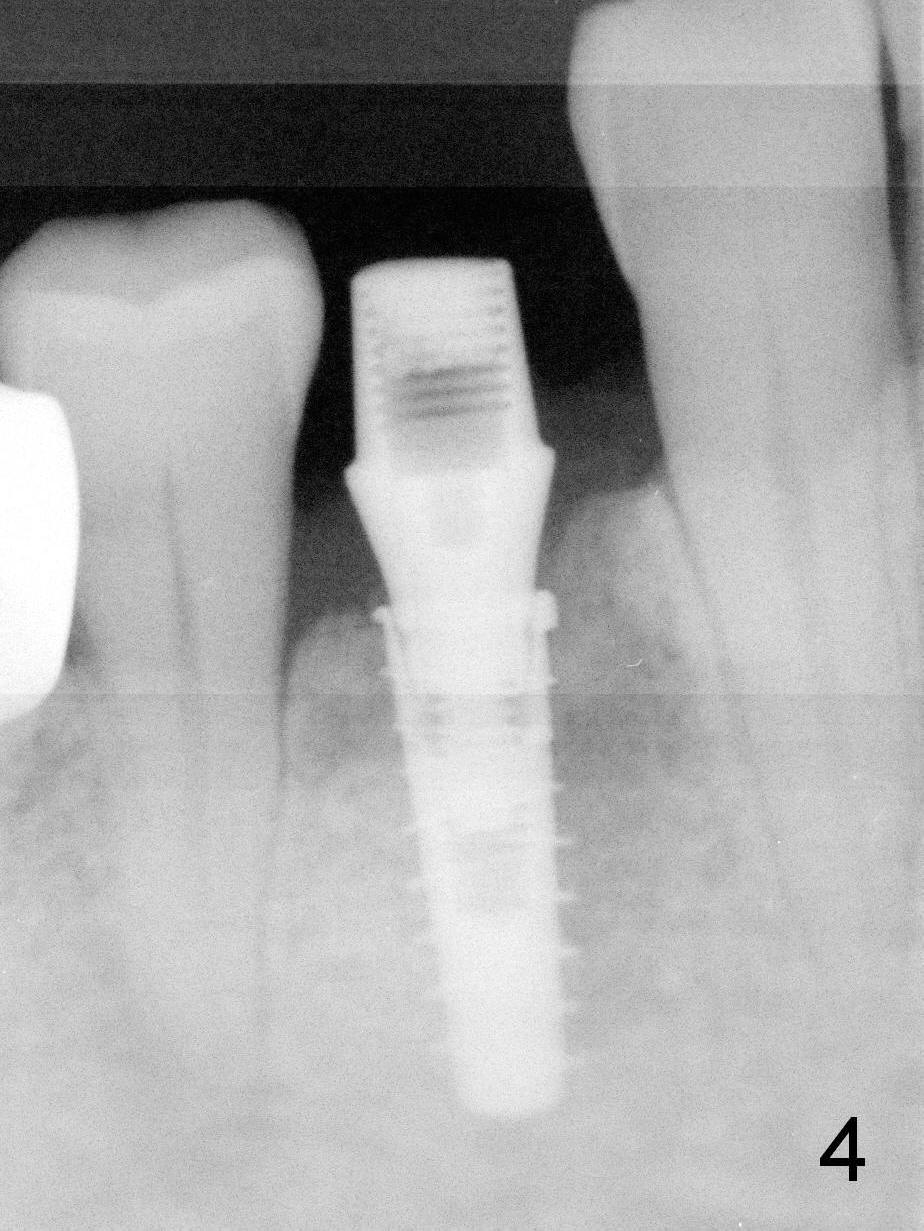

After placement of a 4x11 mm implant, a 4.5x4(2) mm abutment is inserted (Fig.4). Three months postop (Fig.6,7 (incomplete abutment seating (hand tightening))), the implant is loaded for intrusion of the opposing supraerupted tooth.